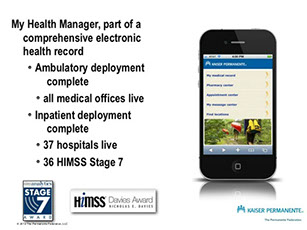

USAA ~ Safeway ~ Limited Brands ~ Macy's ~ Sears ~ Emporium ~ Nokia ~ Motorola ~ Samsung ~ LG ~ BlackBerry ~ HTC ~ Wal-Mart Stores ~ CVS ~ Best Buy ~ Rite Aid ~ Nike ~ GAP ~ J. C. Penney ~ Chevron ~ General Electric ~ AT&T ~ Hewlett-Packard ~ Bank of America Corp. ~ Citigroup ~ Berkshire Hathaway ~ International Business Machines ~ McKesson ~ Kaiser Permanente ~ Kaiser Hospitals ~ U.C.S.F ~ Stanford University School of Medicine/Medical Center ~ Sutter Healthcare ~ California Pacific Medical Center ~ San Francisco General Hospital And Medical Center ~ San Francisco VA Medical Center ~ U.S. Department of Transportation ~ U.S. Department of Homeland Security ~ Exar ~ Boeing ~ AIS ~ Siemens ~ Kaiser People Solutions ~ Cardinal Health ~ Procter & Gamble ~ UnitedHealth Group ~ Kroger ~ Marathon Oil ~ Costco Wholesale ~ Home Depot ~ Target ~ Johnson & Johnson ~ Morgan Stanley ~ State Farm Insurance ~ Dell ~ Boeing ~ Microsoft ~ Walgreen ~ United Technologies ~ Dow Chemical ~ MetLife ~ Wells Fargo ~ United Parcel Service ~ Caterpillar ~ Lowe's ~ Sears Holdings ~ Cisco Systems ~ Johnson Controls ~ FedEx ~ Intel ~ Sysco ~ Comcast ~ Coca-Cola ~ American Express ~ Aetna ~ Motorola ~ Allstate ~ Prudential Financial ~ Tyson Foods ~ Staples ~ Delta Air Lines ~ City and County of Sacramento ~ City and County of San Francisco ~ City and County Oakland ~ San Jose International Airport ~ JFK International Airport